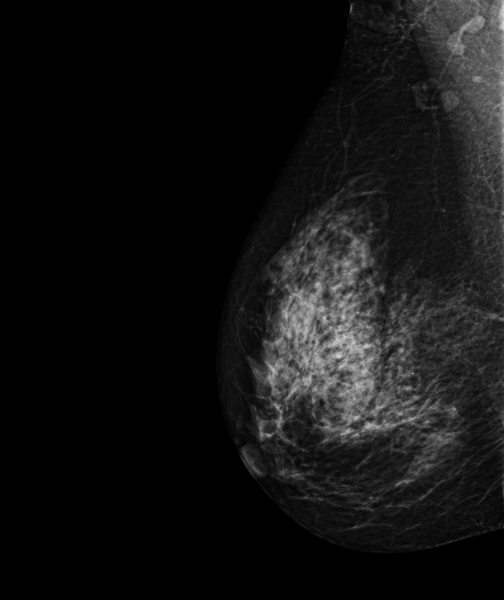

MammoScreen® points to developing asymmetry of the right breast.

Ultrasound confirms an 8 mm hypoechoic formation of the right outer quadrant of the breast 6 cm from the polylobed nipple.

Microbiopsy confirms infiltrating carcinoma SBR 2 RH+.

*Case from the practice of Dr. Le Van An.